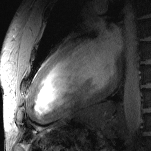

All these efforts culminated in images of the beating heart with a spatial resolution that is by a factor of five superior to that routinely available at 1.5 tesla, and which might come close to turning a 10-megapixel digital camera into a 50-megapixel digital camera. These improvements offer detailed insights into cardiac anatomy and allow accurate delineation of myocardial borders, a feature that is essential for cardiac chamber quantification.

- von Knobelsdorff-Brenkenhoff F, Frauenrath T, Prothmann M, Dieringer MA, Hezel F, Renz W, et al. Cardiac chamber quantification using magnetic resonance imaging at 7 Tesla--a pilot study. Eur Radiol. 2010;20(12):2844-2852.